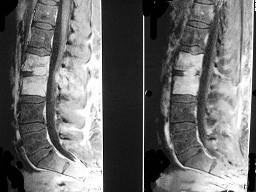

问题 男,53岁,高热,寒战,背痛半月余,请结合影像学检查选出最可能的诊断 ( )

选项 A、强直性脊柱炎 B、椎体压缩骨折 C、脊柱骨髓炎 D、脊柱结核 E、脊柱转移瘤

答案 C